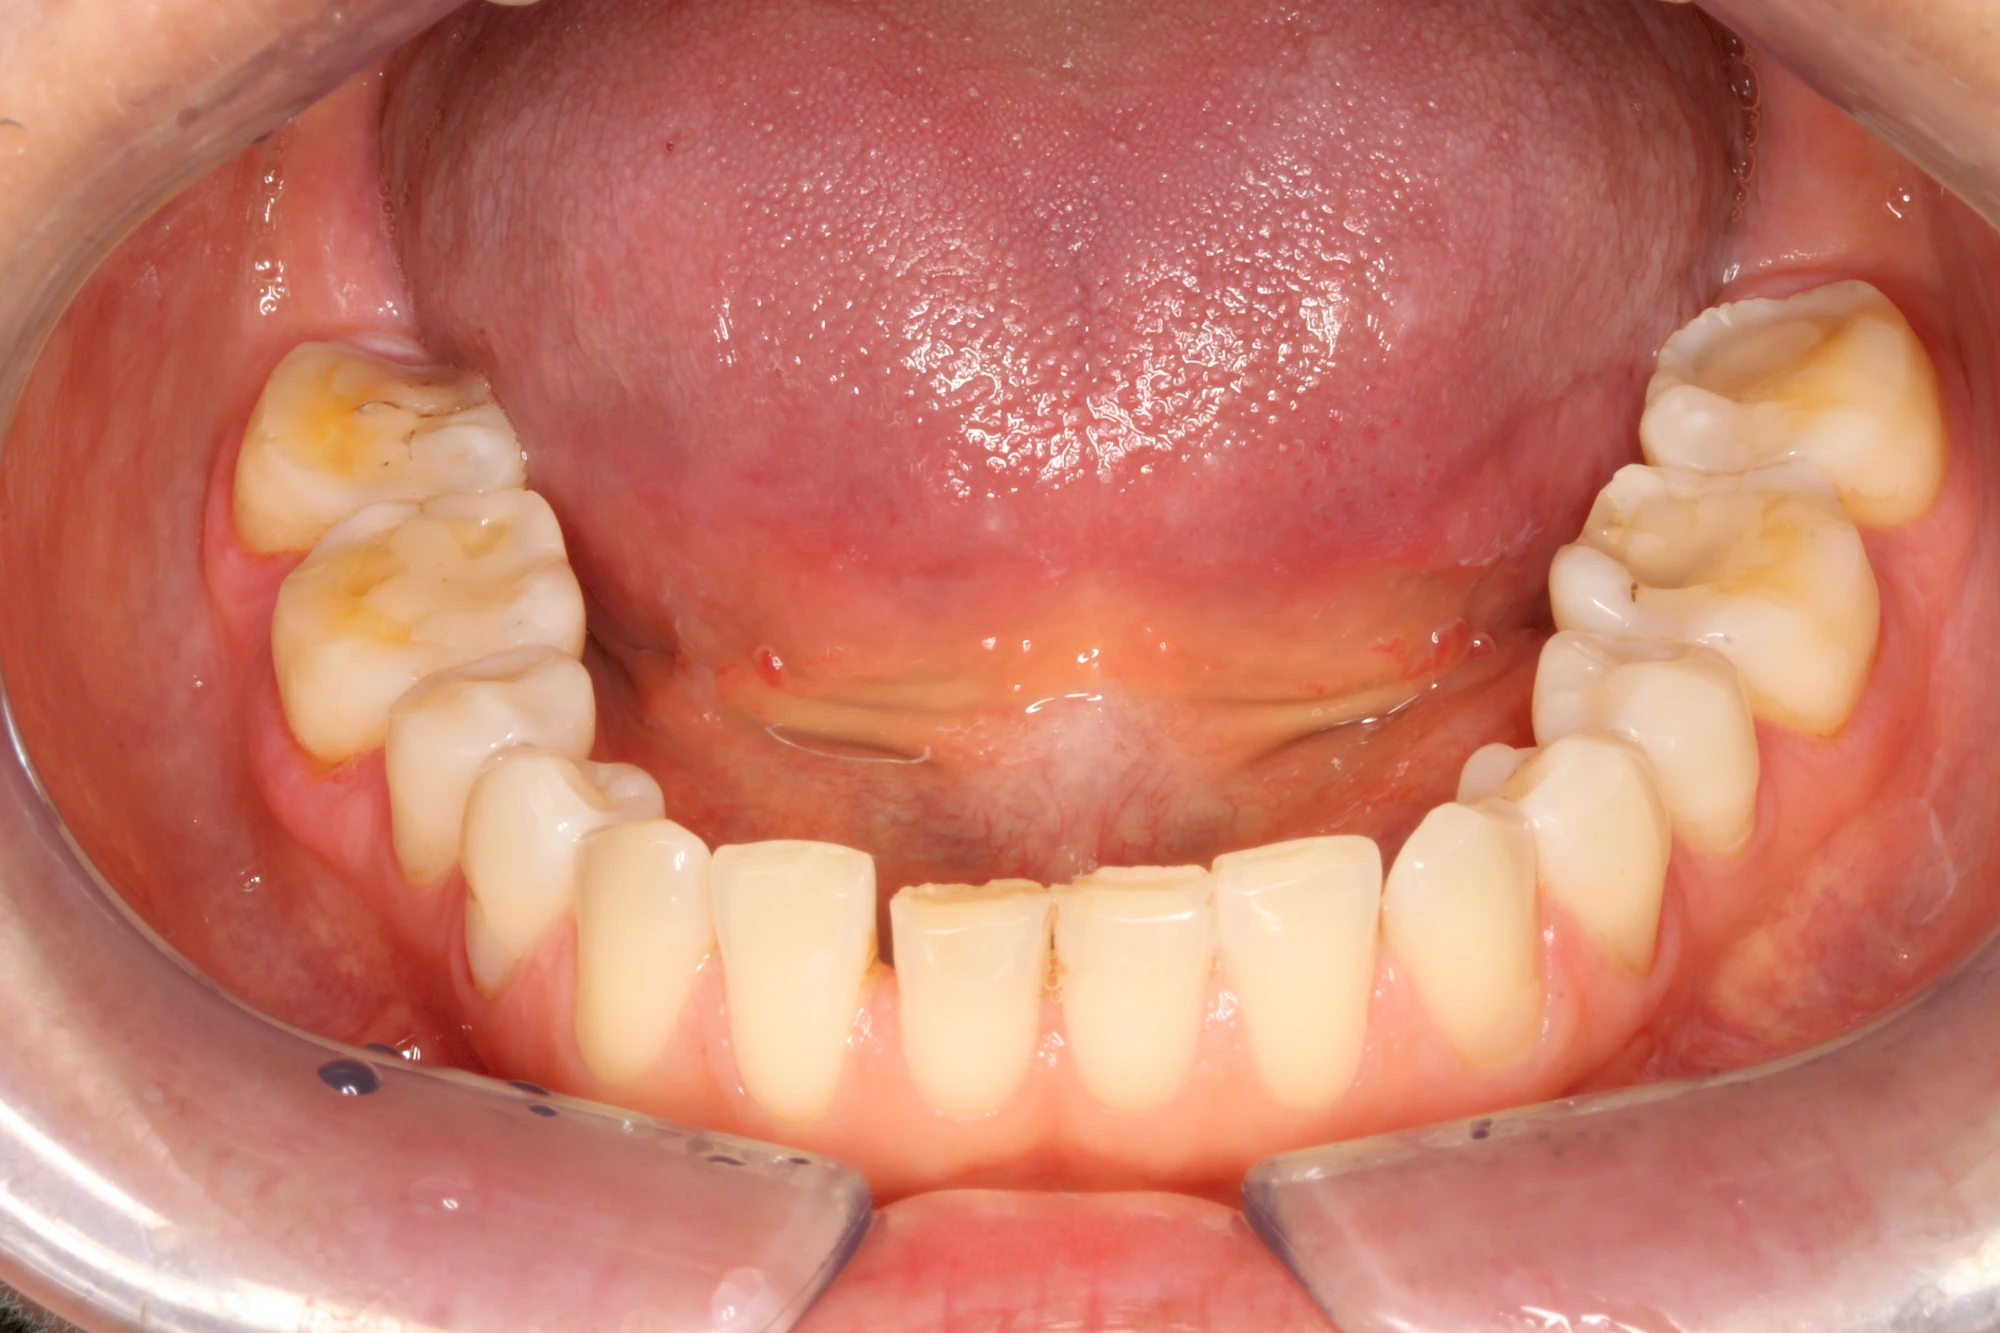

Über die Zeit können verschiedene Prozesse die Zahnhartsubstanzen aufzehren:

- Abnutzung durch Kauen (Abrasion) oder duch durch übermäßiges Knirschen bzw. Pressen (Attrition)

- Säurebedingte Auswaschung (Erosion)

- Knirschen bzw. Pressen und ungünstige Putztechnik (Druck): keilförmige Defekte

Die Zähne können dabei auf Reize (warm, kalt, süß, sauer) oder auch beim Zähneputzen empfindlich oder schmerzhaft sein. In allen diesen Fällen ist es sinnvoll, den Zahnarzt zu kontaktieren und das weitere Vorgehen abzustimmen.